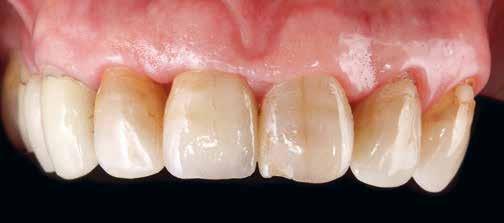

Preoperatív helyzet

Egy fiatal páciens jelentkezett nálunk, akinek eltörött a szabad véggel rendelkező hídja (1. ábra). A hiányzó, első premoláris fog esetén implantációs pótlást javasoltunk. A csontállomány értékeléséhez CBCT-vizsgálatot végeztünk, és az elemzéséhez NNT Viewert (NewTom) használtunk, és copaSKY 4×10 mm-es (bredent medical) implantátumot választottuk a fog pótlásához

1. ábra: Műtét előtti fogászati panorámafelvétel, amelyen a hiányzó felső állcsont jobb első premolárisát és a szabad véggel rendelkező hidat láthatjuk. — 2. ábra: Az implantátum méreteinek megtervezése CBCT-vel. 3. ábra: Bukkális lágyrészdefektus. — 4. ábra: A biológiai szélesség értékelése a vertikális lágyszövetvastagság alapján. 5. ábra: Palatinális „tekercslebeny” – Palatal roll flap. — 6. ábra: Bredent medical copaSKY 4x10 implantátumbeültetés. 7. ábra: Szubkresztális implantátumbeültetés a várható biológiai szélességnek megfelelően.